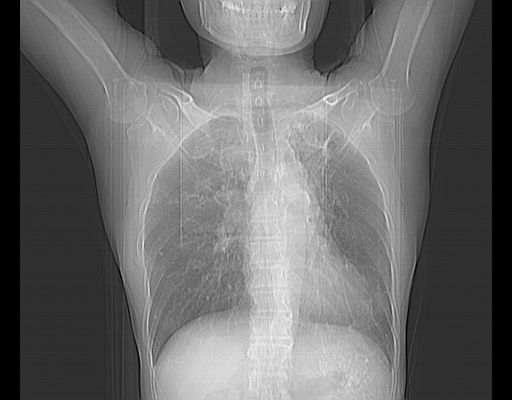

男,59岁,“结核性胸膜炎”30余年,胸部经常疼痛,多次x检查提示“肺部”炎症。腹部疼痛5日,b超提示:“肝内短管结石,余显示不清,建议进一步检查。”

两肺结核并右侧胸腔积液;脾脏、腹腔及腹膜后淋巴结结核[陈旧性];肝内胆管结石

胸部腹部都是结核(双肺。纵隔淋巴结,肝脏,脾脏,肠系膜)

两肺结核并右侧胸腔积液;脾脏、腹腔及腹膜后淋巴结结核[陈旧性];肝内胆管结石。直肠息肉?